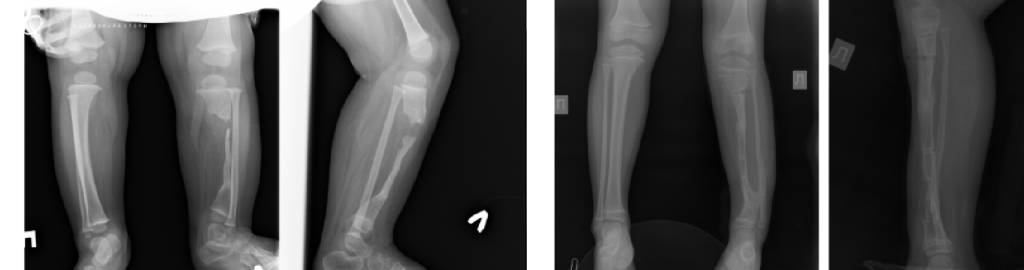

Main areas of surgical work: